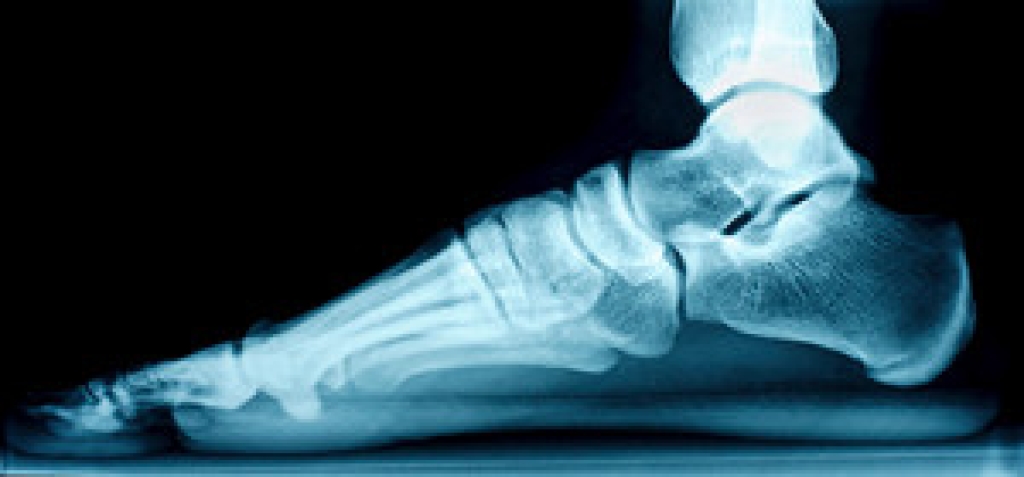

In order to diagnose your bunion, your podiatrist may ask about your medical history, symptoms, and general health. Your doctor might also order an x-ray to take a closer look at your feet. Nonsurgical treatment options include orthotics, padding, icing, changes in footwear, and medication. If nonsurgical treatments don’t alleviate your bunion pain, surgery may be necessary.